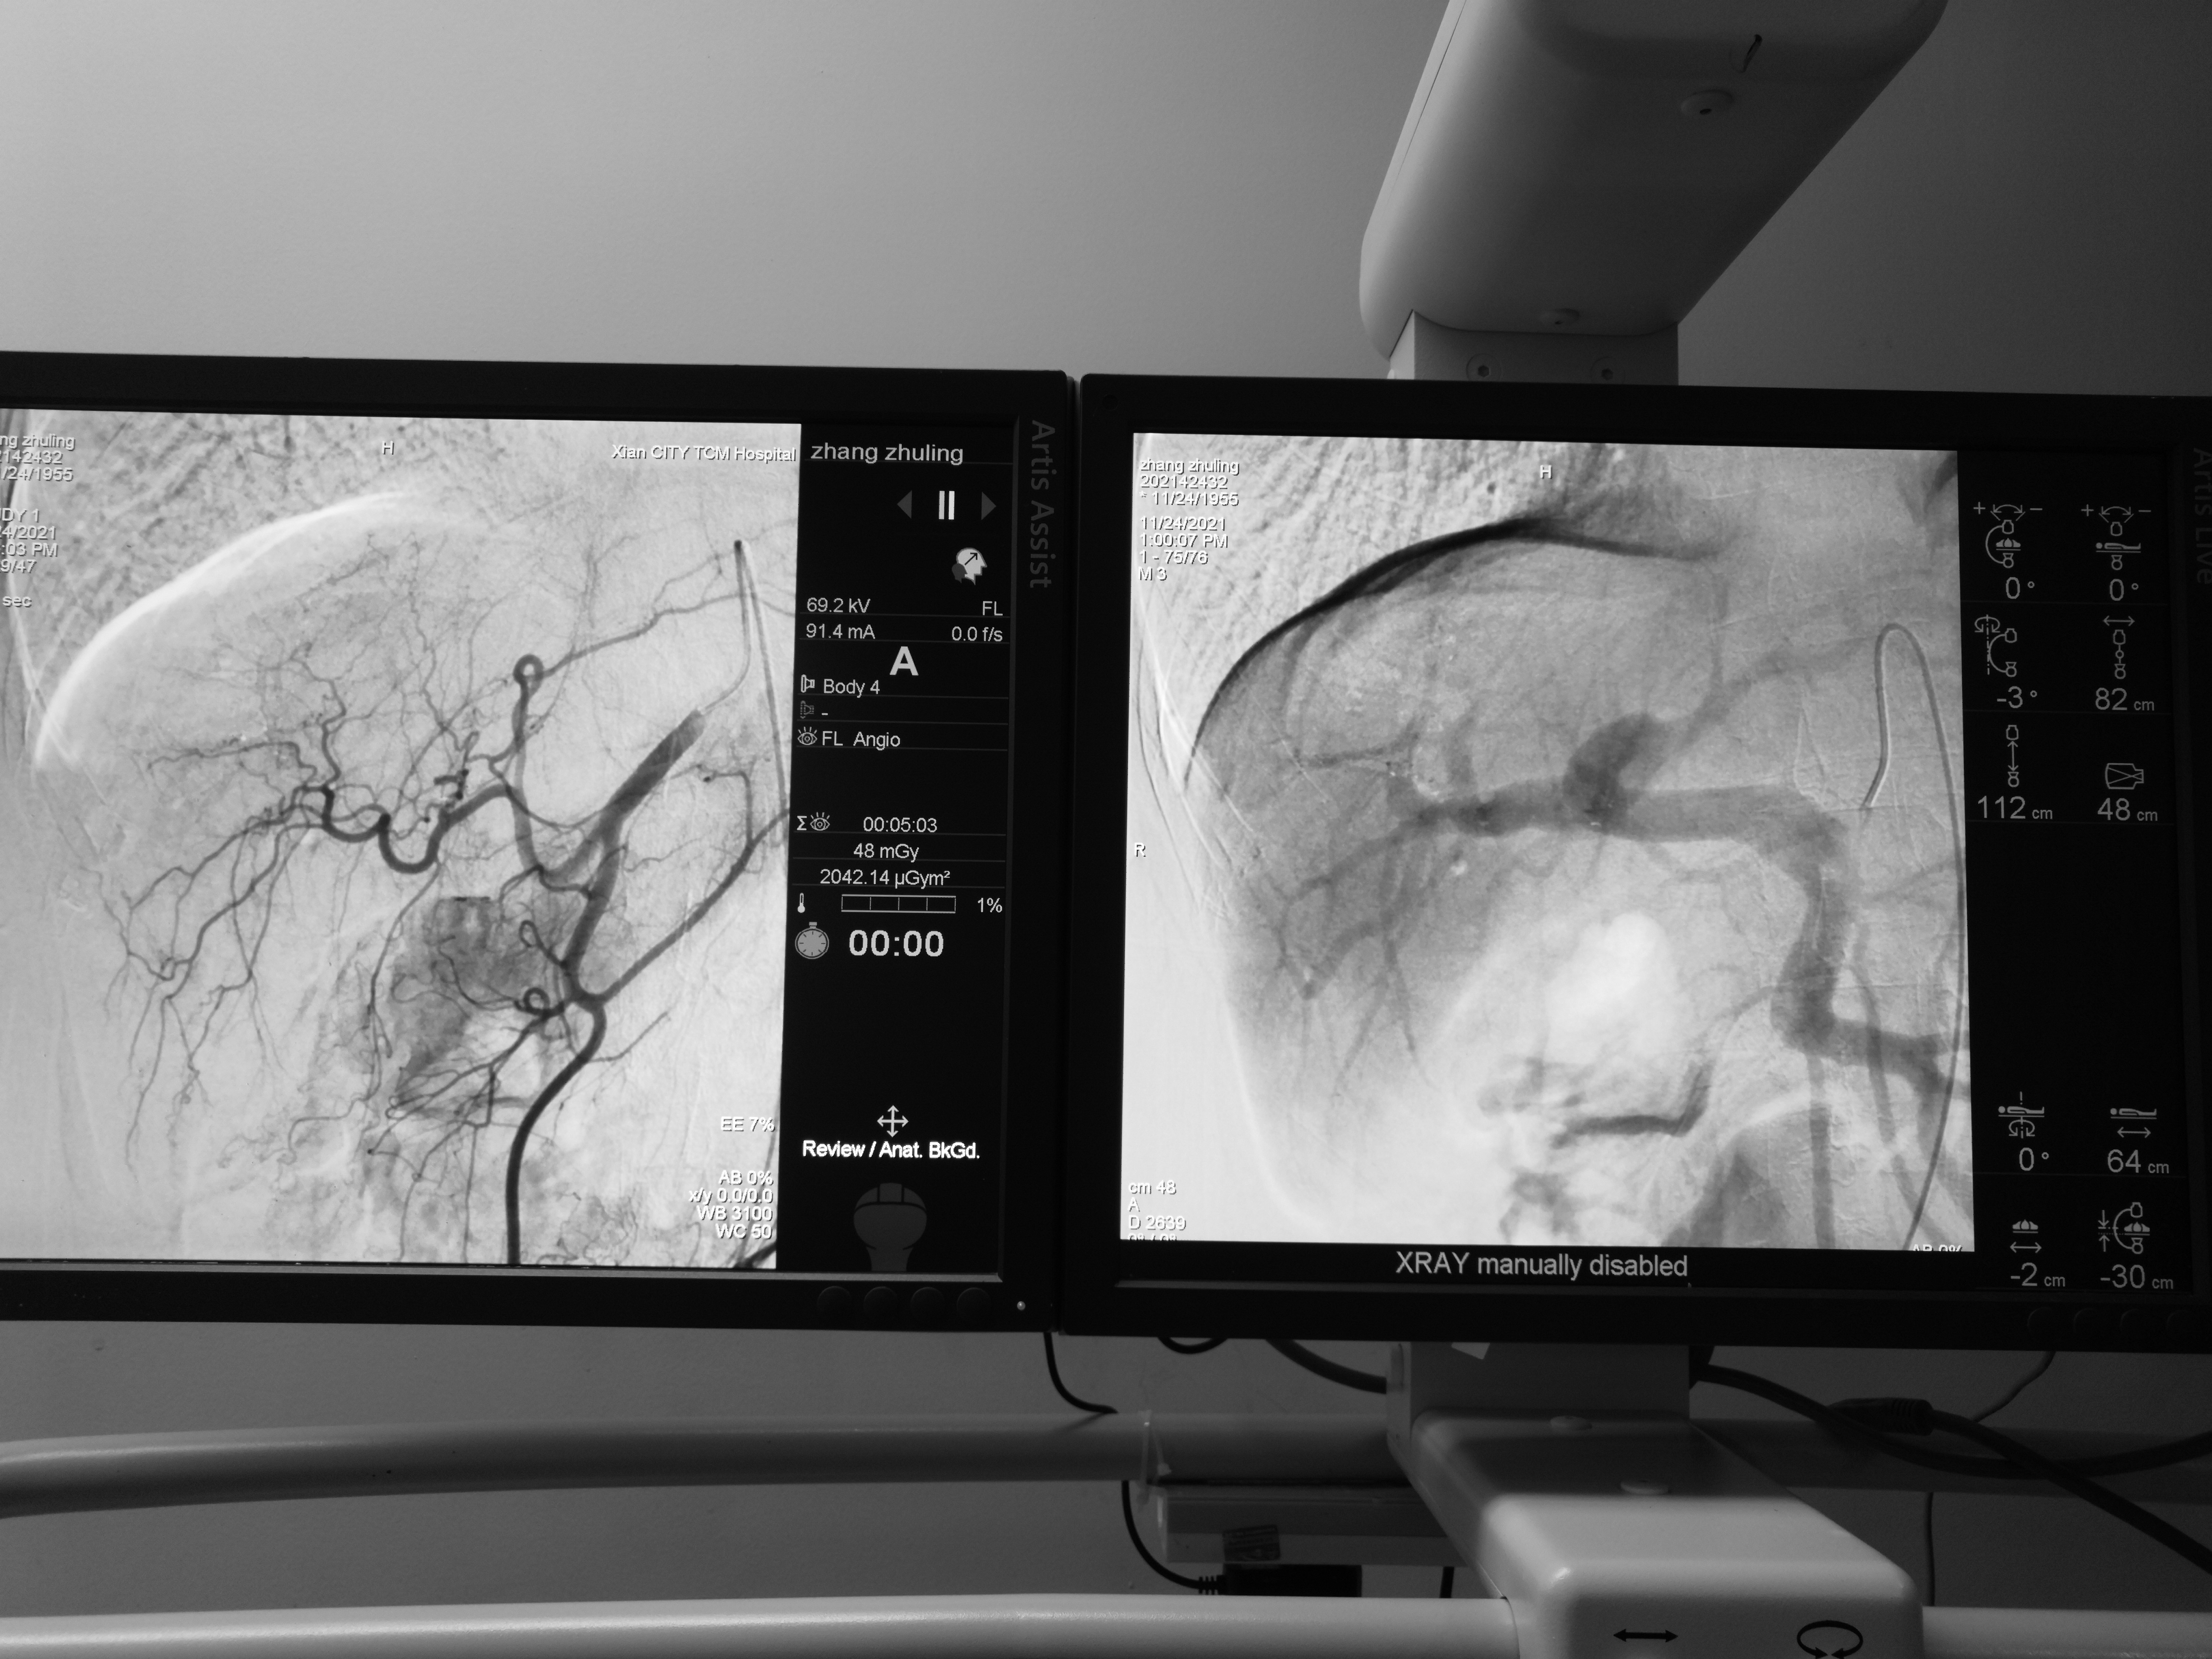

例如这个肠癌术后肝转移的病人,结肠没有新发病灶,所以先肝动脉化疗栓塞(机枪扫射)灭活大片肿瘤,再细针穿刺消融(*击狙**步枪点射)灭活三个顽固分子,最大程度的保存正常肝脏,最大程度的消灭肿瘤。伤口只有一个针眼,体现了现代医学 “微创无痛,原装出院” 的理念。

第一步:肝转移瘤动脉灌注化疗+栓塞